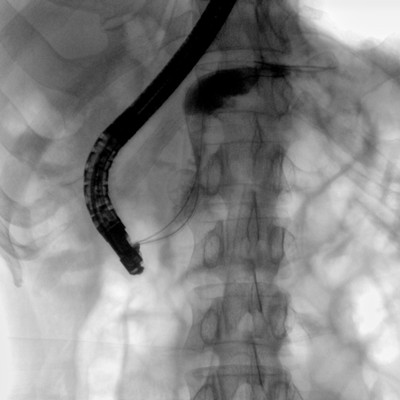

消化內(nèi)科: ERCP、PTCD、肝臟介入(TACE、灌注)、食管支架等。

優(yōu)質(zhì)平板探測器、可靈活升降調(diào)節(jié)SID、獨特圖像處理系統(tǒng)、高品質(zhì)濾線柵,大視野成像清晰不失真。